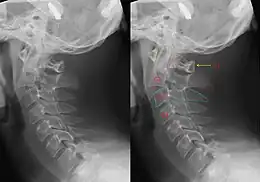

Although a hangman's fracture is unstable, survival from this fracture is relatively common, as the fracture itself tends to expand the spinal canal at the C2 level. It is not unusual for patients to walk in for treatment and have such a fracture discovered on X-rays. Only if the force of the injury is severe enough that the vertebral body of C2 is severely subluxed from C3 does the spinal cord become crushed, usually between the vertebral body of C3 and the posterior elements of C1 and C2.

As a result, Barsa and coauthors showed that the result of fracture fusion reduced after one year but only one patient died of other disease during the follow-up.[8] Hakalo and Wronski (2008) showed the benefits of operative treatment such as using transoral C2-C3 discectomy with plate-cage stabilization or posterior direct pars screw repair for the reducing and healing process.[9] In deliberate or suicidal hanging, asphyxia is much more likely to be the cause of death due to associated prevertebral swelling. A common sign is a constricted pupil (Horner's syndrome) on the ipsilateral side due to loss of sympathetic innervation to the eye, caused by damage to the sympathetic trunk in the neck.